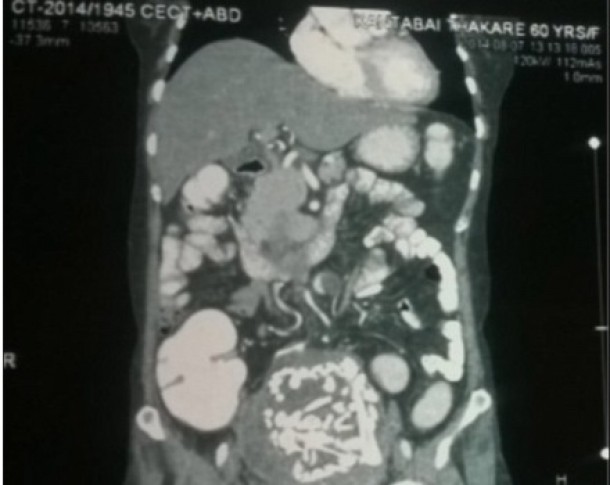

Doctorii au simtit ce credeau a fi un nodul in partea stanga si au descoperit o masa alcatuita din materie calcifiata. Initial, ei au crezut ca femeia are cancer. Dar dupa ce a fost supusa altor interventii, s-a descoperit ca in toti acesti ani ea a purtat copilul mort in pantece.

Cand doctorii au intrebat-o cateva lucruri despre trecutul ei medical, femeia le-a spus ca a fost insarcinata in 19778, dar copilul ei a murit. Le-a mai spus ca s-a speriat si ca a mers acasa, in satul ei, fara ca medici sa ii scoata fatul din abdomen. Femeia doar a luat un tratament de la un centru local de sanatate. Situatia in care se afla femeia ar putea fi considerata drept cea mai lunga sarcina ectopica din lume, spun specialistii.